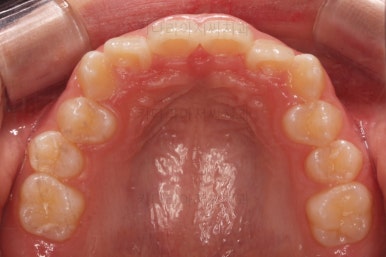

초진 시 입안의 모습입니다.

앞니가 안으로 굽어 들어간 양상인데요. 흔히 "옥니"라고 표현합니다.(뻐드렁니의 반대개념)

전반적으로 치열이 삐뚤삐뚤하고요.

그리고 전반적으로 아래 치열이 윗니에 비해 뒤로 밀려 있어서, 어금니의 맞물림이 좋지 못하고 듬성듬성해 보이는 상황이었어요.